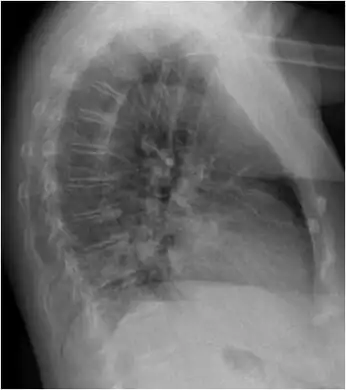

a-d)CTs of individual with Chlamydia psittaci infection -

Chest X-ray shows patchy retrocardial infiltrate.